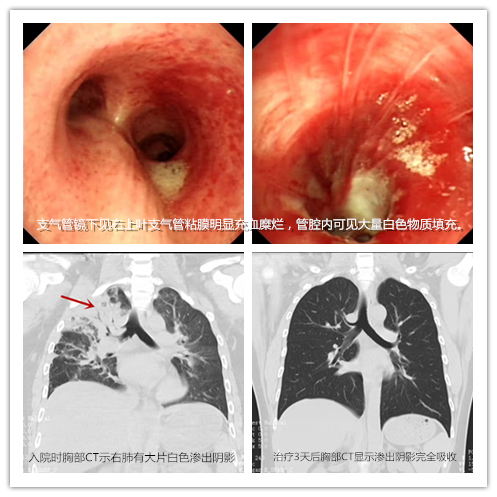

1月26日,益阳小伙小宁和朋友在长沙聚会,“豪爽”喝酒后,因昏迷不醒被送到捷克论坛 急诊二部抢救。入院时,小宁呼吸急促,血氧饱和度下降,经积极抢救后终于苏醒,但仍感明显呼吸困难,查胸部CT显示其右主支气管及中叶支气管内可见絮状阴影,右肺有大片白色渗出阴影,被诊断为吸入性肺炎收住呼吸五病区。入院后,经过支气管镜肺泡灌洗、抗感染等及时、积极的治疗,患者病情逐渐好转,即将在春节前出院。